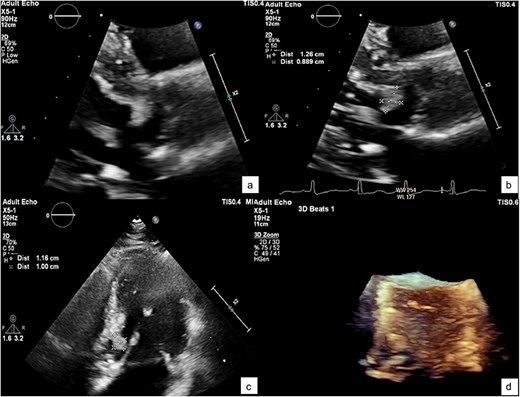

He was referred to our hospital for further evaluation by the cardiology and cardiothoracic surgery departments. On admission, he was afebrile with a heart rate of 62 beats per minute, blood pressure of 148/73 mmHg, and respiratory rate of 20 breaths per minute. No abnormalities were noted in any other system. Laboratory findings were unremarkable. An ECG demonstrated normal sinus rhythm. TTE re-evaluation revealed a normal LVEF of 72% with a 1.2 × 1 cm hypermobile cardiac mass attached to the basal anteroseptal wall near the LVOT without evidence of LVOT obstruction; there were no valvular lesions or thrombus seen (Figs 1 and 2). Coronary angiography showed normal coronary vessels. Due to its nature and clinical presentation, the patient was set for early surgical excision of the mass 3 days after admission.

A TTE showing a small-rounded mass attached to the LV septum (arrow), which can be seen protruding into the LVOT in various echocardiographic views: Parasternal view (a), parasternal long axis view (b), 5-chamber view (c), and short-axis view of aortic valve (d).